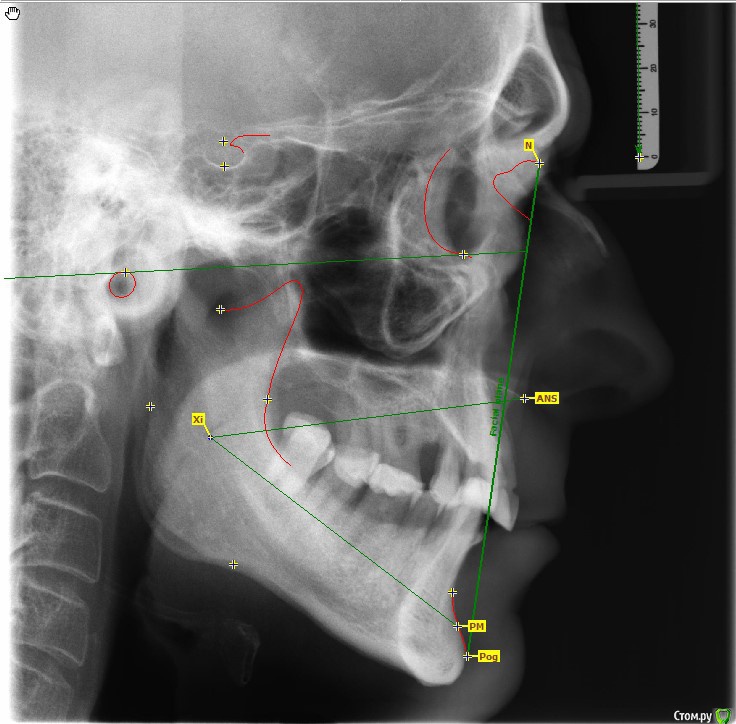

Stomka Опубликовано 14 февраля, 2016 Поделиться Опубликовано 14 февраля, 2016 Я на курсы к Будовскому не ходил, пытаюсь пока сам понять. Если каких точек не хватает, я расставлю. Угол ANSXiPM в пределах нормы, что (как я думаю) позволяет вынести решение о том, что нижняя челюсть "съехала назад" (об этом говорит угол NPogPOr). Совместно с выраженным феноменом Попова-Годона кажется, что высота прикуса весьма занижена (в боковых отделах между окклюзионной поверхностью и альвеолярной десной 2-4 мм). Если мои суждения верны, каким образом я могу вернуть положение нижней челюсти и что делать с боковой группой зубов?P.S. я очень стесняюсь, но правда не знаю, что делать, потому большая просьба не стебаться) Ссылка на комментарий